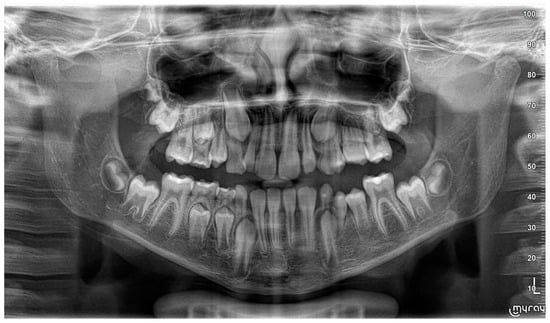

3. Follow-Up and Outcomes